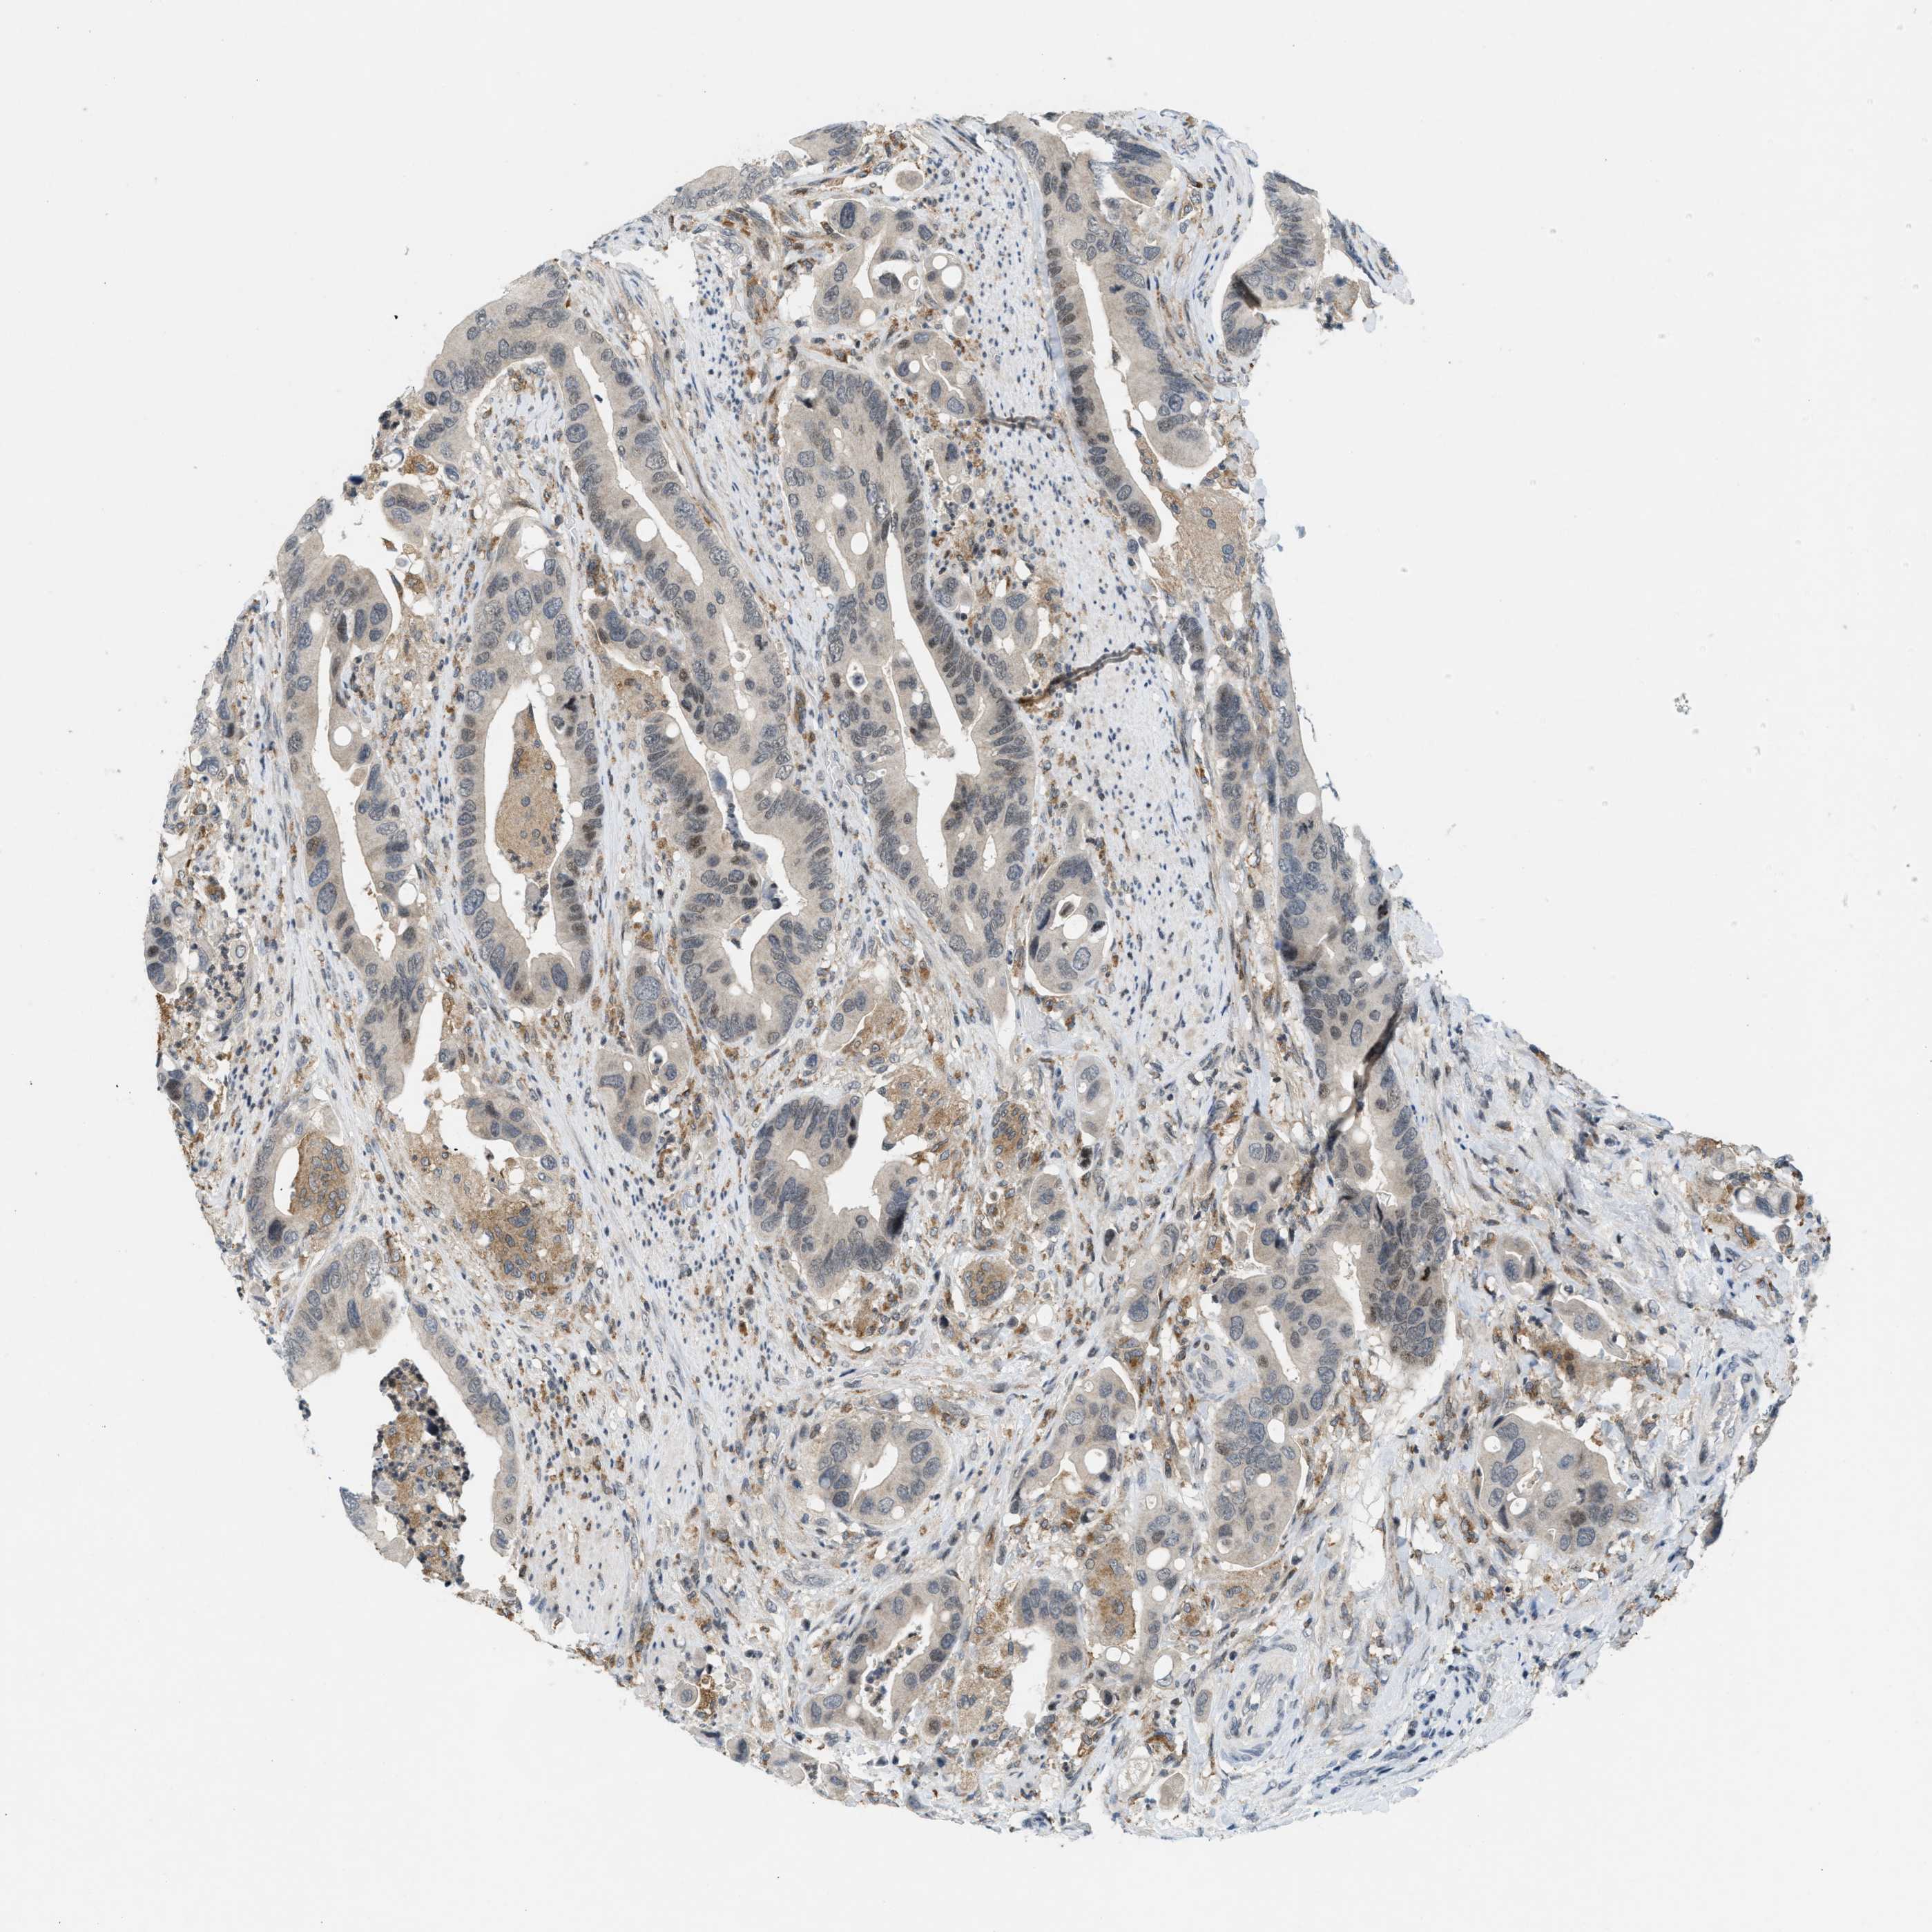

CANCER COLORECTAL CANCER Show tissue menu

COAD TCGA COAD VALIDATION READ TCGA READ VALIDATION PROTEIN COAD CPTAC PROTEIN EXPRESSION

ANTIBODIES

AND

VALIDATION